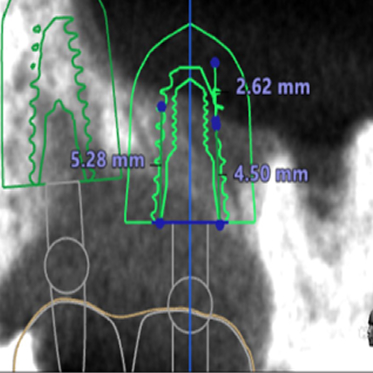

● 上の顎の奥歯にインプラントを入れるのに骨が足りないため、ソケットリフトと人工骨補填して骨造成を行った症例1

術前

藤沢デンタルオフィスのインプラント術前 藤沢デンタルオフィスのインプラント術前

3Dシミュレーション

術後

藤沢デンタルオフィスのインプラント術後 藤沢デンタルオフィスのインプラント術後

シミュレーション通りの上顎洞底挙上と人工骨補填(3Dガイドシステム使用)